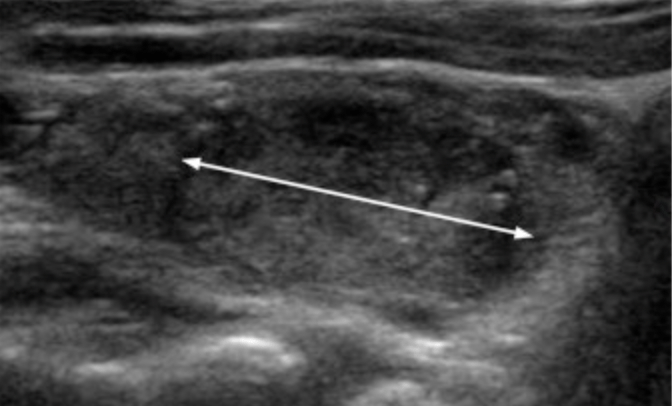

- Measurement and Documentation:

- Accurate sizing of thyroid nodules is critical, as the maximum dimension determines whether a given lesion should be biopsied or followed

- Although some interobserver discrepancy is inevitable because of variable conspicuity, consistent technique improves measurement accuracy and reproducibility

- Nodules should be measured in three axes:

- Maximum dimension on an axial image

- Maximum dimension perpendicular to the previous measurement on the same image

- Maximum longitudinal dimension on a sagittal image

- For obliquely oriented nodules, these measurements may be different than the ones used to determine a taller-than-wide shape, but this discrepancy should rarely present a problem in practice

- Measurements should also include:

- The nodule’s halo, if present

- Practitioners may use linear dimensions to determine volume, a calculation that is available on many ultrasound machines

- Regardless of the method used, each practice should measure and report nodules consistently to facilitate serial comparison